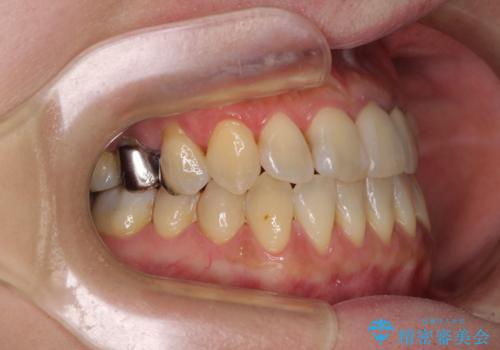

反対咬合で痛む前歯を改善 インビザラインによる矯正治療

- 前歯の反対咬合により、日々強い痛みを感じているとのことで来院された患者様です。

骨格的に下顎が前方位にありますが、歯列矯正で前歯の被蓋関係を改善することができると判断されたため、インビザラインにより矯正治療を行うこととしました。

また、上顎前歯と下顎大臼歯に神経を取り除いた歯があったため、矯正治療後に、セラミッククラウンにて補綴することとしました。

前歯が内側に倒れ込む力がかかり、正常な歯ぎしりもできないため、非常に負担のかかりやすい咬み合わせでした。

矯正治療中に上顎前歯が下顎前歯を乗り越える際は、前歯でしか咬めない状況が続くため、食事など不便を感じましたが、治療後には前歯の痛みもなくなり、安定した咬み合わせとなりました。